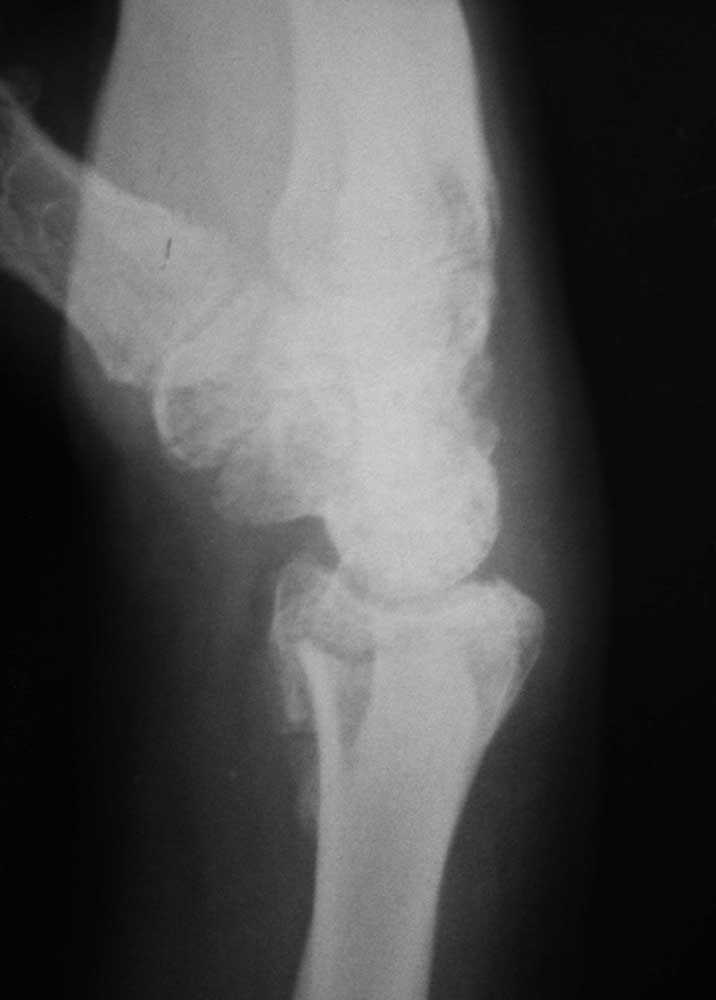

То же самое, только в профиль

Как я понял, срок иммобилизации составил 3 месяца! Описанная Вами функция лучезапястного сустава (странно, что не указана функция кисти) вполне соответствует этому. Дальше нужно определиться что лечить: рентгенограмму или больного. В первом варианте оправдано выполнение корригирующей остеотомии с костной аутопластикой. Выбор фиксации, ЧКДО или locking plate, зависит от Ваших предпочтений. В итоге получите красивую ретгенкартинку и кисть с функцией ласты. Плавать будет быстро.

мне кажется, можно попробовать дозированное исправление деформации в аппарате. Учитывая сроки, остеотомия на уровне "шипа" дистального отломка, выращивание трапециевидного регенерата.

правая кисть - прямая проекция и разные степени проекции

боковая и косая полупронированная проекции